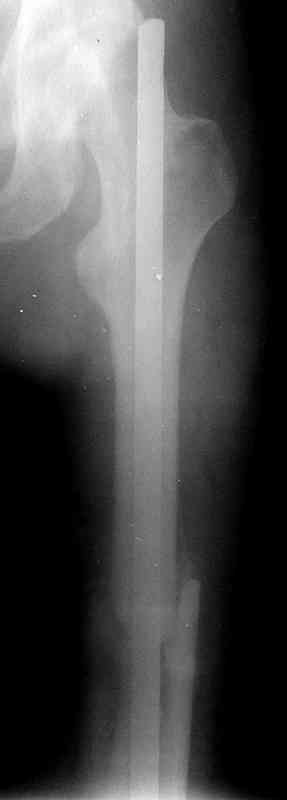

Уважаемые коллеги!На прилагаемых снимках - состояние после оперативного вмешательства (открытый перелом левого бедра в средней трети):

МОС, стержень нефиксированный. С момента операции прошло 8 месКак по Вашему мнению происходит консолидация? Допустимо ли смещение или необходима повторная операция по выравниванию конечности? Если да, какой метод рекомендуете (фиксированный стержень, пластина)?Буду благодарен за оперативный ответ.

Вы не пишете, есть ли сейчас болезненные проявления, и какие. Как пациент ходит. Какова функция колена. Ось выглядит приемлемо. Рентгенологически на сращение непохоже. Если есть клиника несращения (боль, хромота), то лучший выбор - закрыто рассверлить и перештифтовать блокированным гвоздем. Желательно определиться поточнее, нет ли проблемы с длиной , чтобы попутно и ее решить. И не создать. Ну и прежде всего исключить инфекцию. Если это инфицицированное несращение, план надо другой.

При таком диаметре штифта не удивительно, что перелом не сросся (кстати, какой диаметр и что за модификация штифта?).

Сегодня фотография открылась...беру свои слова назад: перелом явно в расширенном участке бедра. Целесообразней всего динамический блокирующий остеосинтез.

Ротации конечности у больного нет?